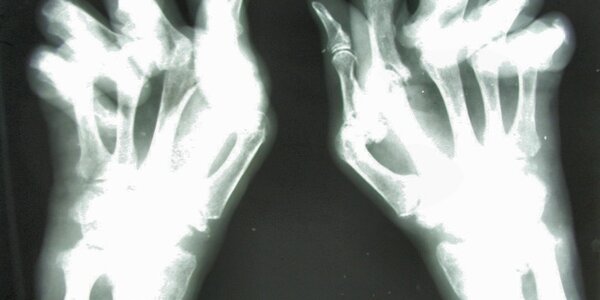

Rheumatoid Arthritis - Can New Treatment Spell The Beginning Of A Cure?

Portuguese scientists have just published a revolutionary new approach to treat rheumatoid arthritis (RA) which, if translated to humans, can change the way we treat autoimmunity (and so diseases like RA but also diabetes and MS) and, with it, the lives of millions of patients The new treatment by Joana Duarte, Luis Graca and colleagues from the Instituto de Medicina Molecular (IMM) in Lisbon is remarkable because it specifically stops the abnormal immunological response behind RA without touching the rest of the immune system, and a short treatment has long lasting effects suggesting that it…